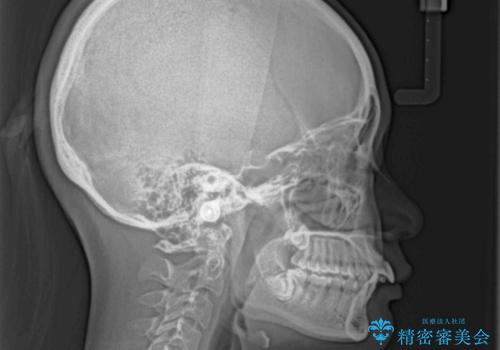

舌の突出癖の影響で、歯列が前方に飛び出いた形態となっている状態でした。

抜歯矯正とするような歯列ではないため、舌のトレーニングを行いながら歯列を側方に拡大させることで口元の突出感を改善することとしました。

横顔は元々突出した印象ではなかったのですが、上顎前歯の角度が改善したことで、唇の閉じにくさが改善されました。